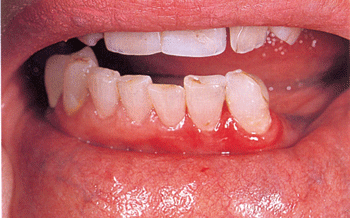

Սովորաբար բերանի խոռոչում բշտեր չեն հայտնաբերվում, չնայած դրանցով է սկսվում այս հիվանդությունը: Բանն այն է, որ գոյացած բշտերն ունենալով բարակ, թառամ, ոչ կայուն ծածկ, շատ շուտ պատռվում են` վերածվելով հիպերեմիկ, խոնավ մակերեսով էրոզիաների, իսկ բաց տեղամասերում` նաև շճային ու շճաարյունային կեղևների (շրթունքների կարմիր երիզ): Ստորև բերված նկարներում ներկայացված է սովորական բշտախտի կլինիկական պատկերը` շրթունքների արտաքին մակերեսի (նկ.5), ներսային մակերեսի (նկ.6), բերանի խոռոչի լորձաթաղանթի (նկ.7) և փափուկ քիմքի (նկ.8) ընդգրկումով: Ախտահարված այս տեղամասերն ուշադիր զննելիս դժվար չէ նկատել, որ էրոզիաները գոյացել են արտաքինից անփոփոխ հյուսվածքի մակերեսի վրա, ի տարբերություն բշտախտ հիշեցնող այլ հիվանդությունների:

Նկար 5. Շրթունքի կարմիր երիզի ախտահարում (բշտախտային էրոզիաներ) |

Նկար 6. Լնդերի և

շրթունքների լորձաթաղանթի ախտահարում |